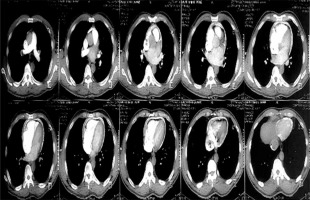

Figure 3

Computed tomography scan of one of the patients showing the calcification ring of calcific constrictive pericarditis

Chest X-ray in patients with constrictive pericarditis may show small or normal cardiac size but presence of cardiomegaly does not rule out constriction [7]. Presence of pericardial calcification – best seen on anterior, oblique or lateral views – is highly suggestive of chronic constrictive pericarditis [1]. However, it has been reported in less than 30% of surgically confirmed cases of constrictive pericarditis [11, 13, 16]. This is consistent with our current study where 2 (20%) out of the ten cases studied showed calcification on both the chest and CT scan, as shown in Figures 2 and 3. Far superior diagnostic yields are achieved with the use of echocardiogram, cardiac CT or magnetic resonance imaging (MRI) [13]. Cardiac CT scan or MRI provides a better assessment of pericardial thickness and calcifications and visualization of any abnormal ventricular contours caused by the constriction [11, 16]. Echocardiography features indicative of constrictive physiology include respiration-related ventricular septal shift, preserved or increased medial mitral annular e-velocity and prominent hepatic vein expiratory diastolic flow reversals [17]. Currently, the use of cardiac catheterization in the diagnosis of constrictive pericarditis is decreasing due to the increased diagnostic accuracy of echocardiography, CT scanning and MRI [13]. However, cardiac catheterization is the gold standard for diagnosis in the event of indeterminate findings with the non-invasive tests [11]. The current study employed two main modalities to confirm the diagnosis of constrictive pericarditis, namely chest CT scan and echocardiography with supporting evidence from chest X-ray and ECG. Six (60%) out of the 10 patients had ECG, 9 had chest X-ray, 8 had echocardiography and 4 had chest CT scan. Three (30%) had confirmation of the diagnosis from both echocardiography and chest CT scan, as shown in Table II.